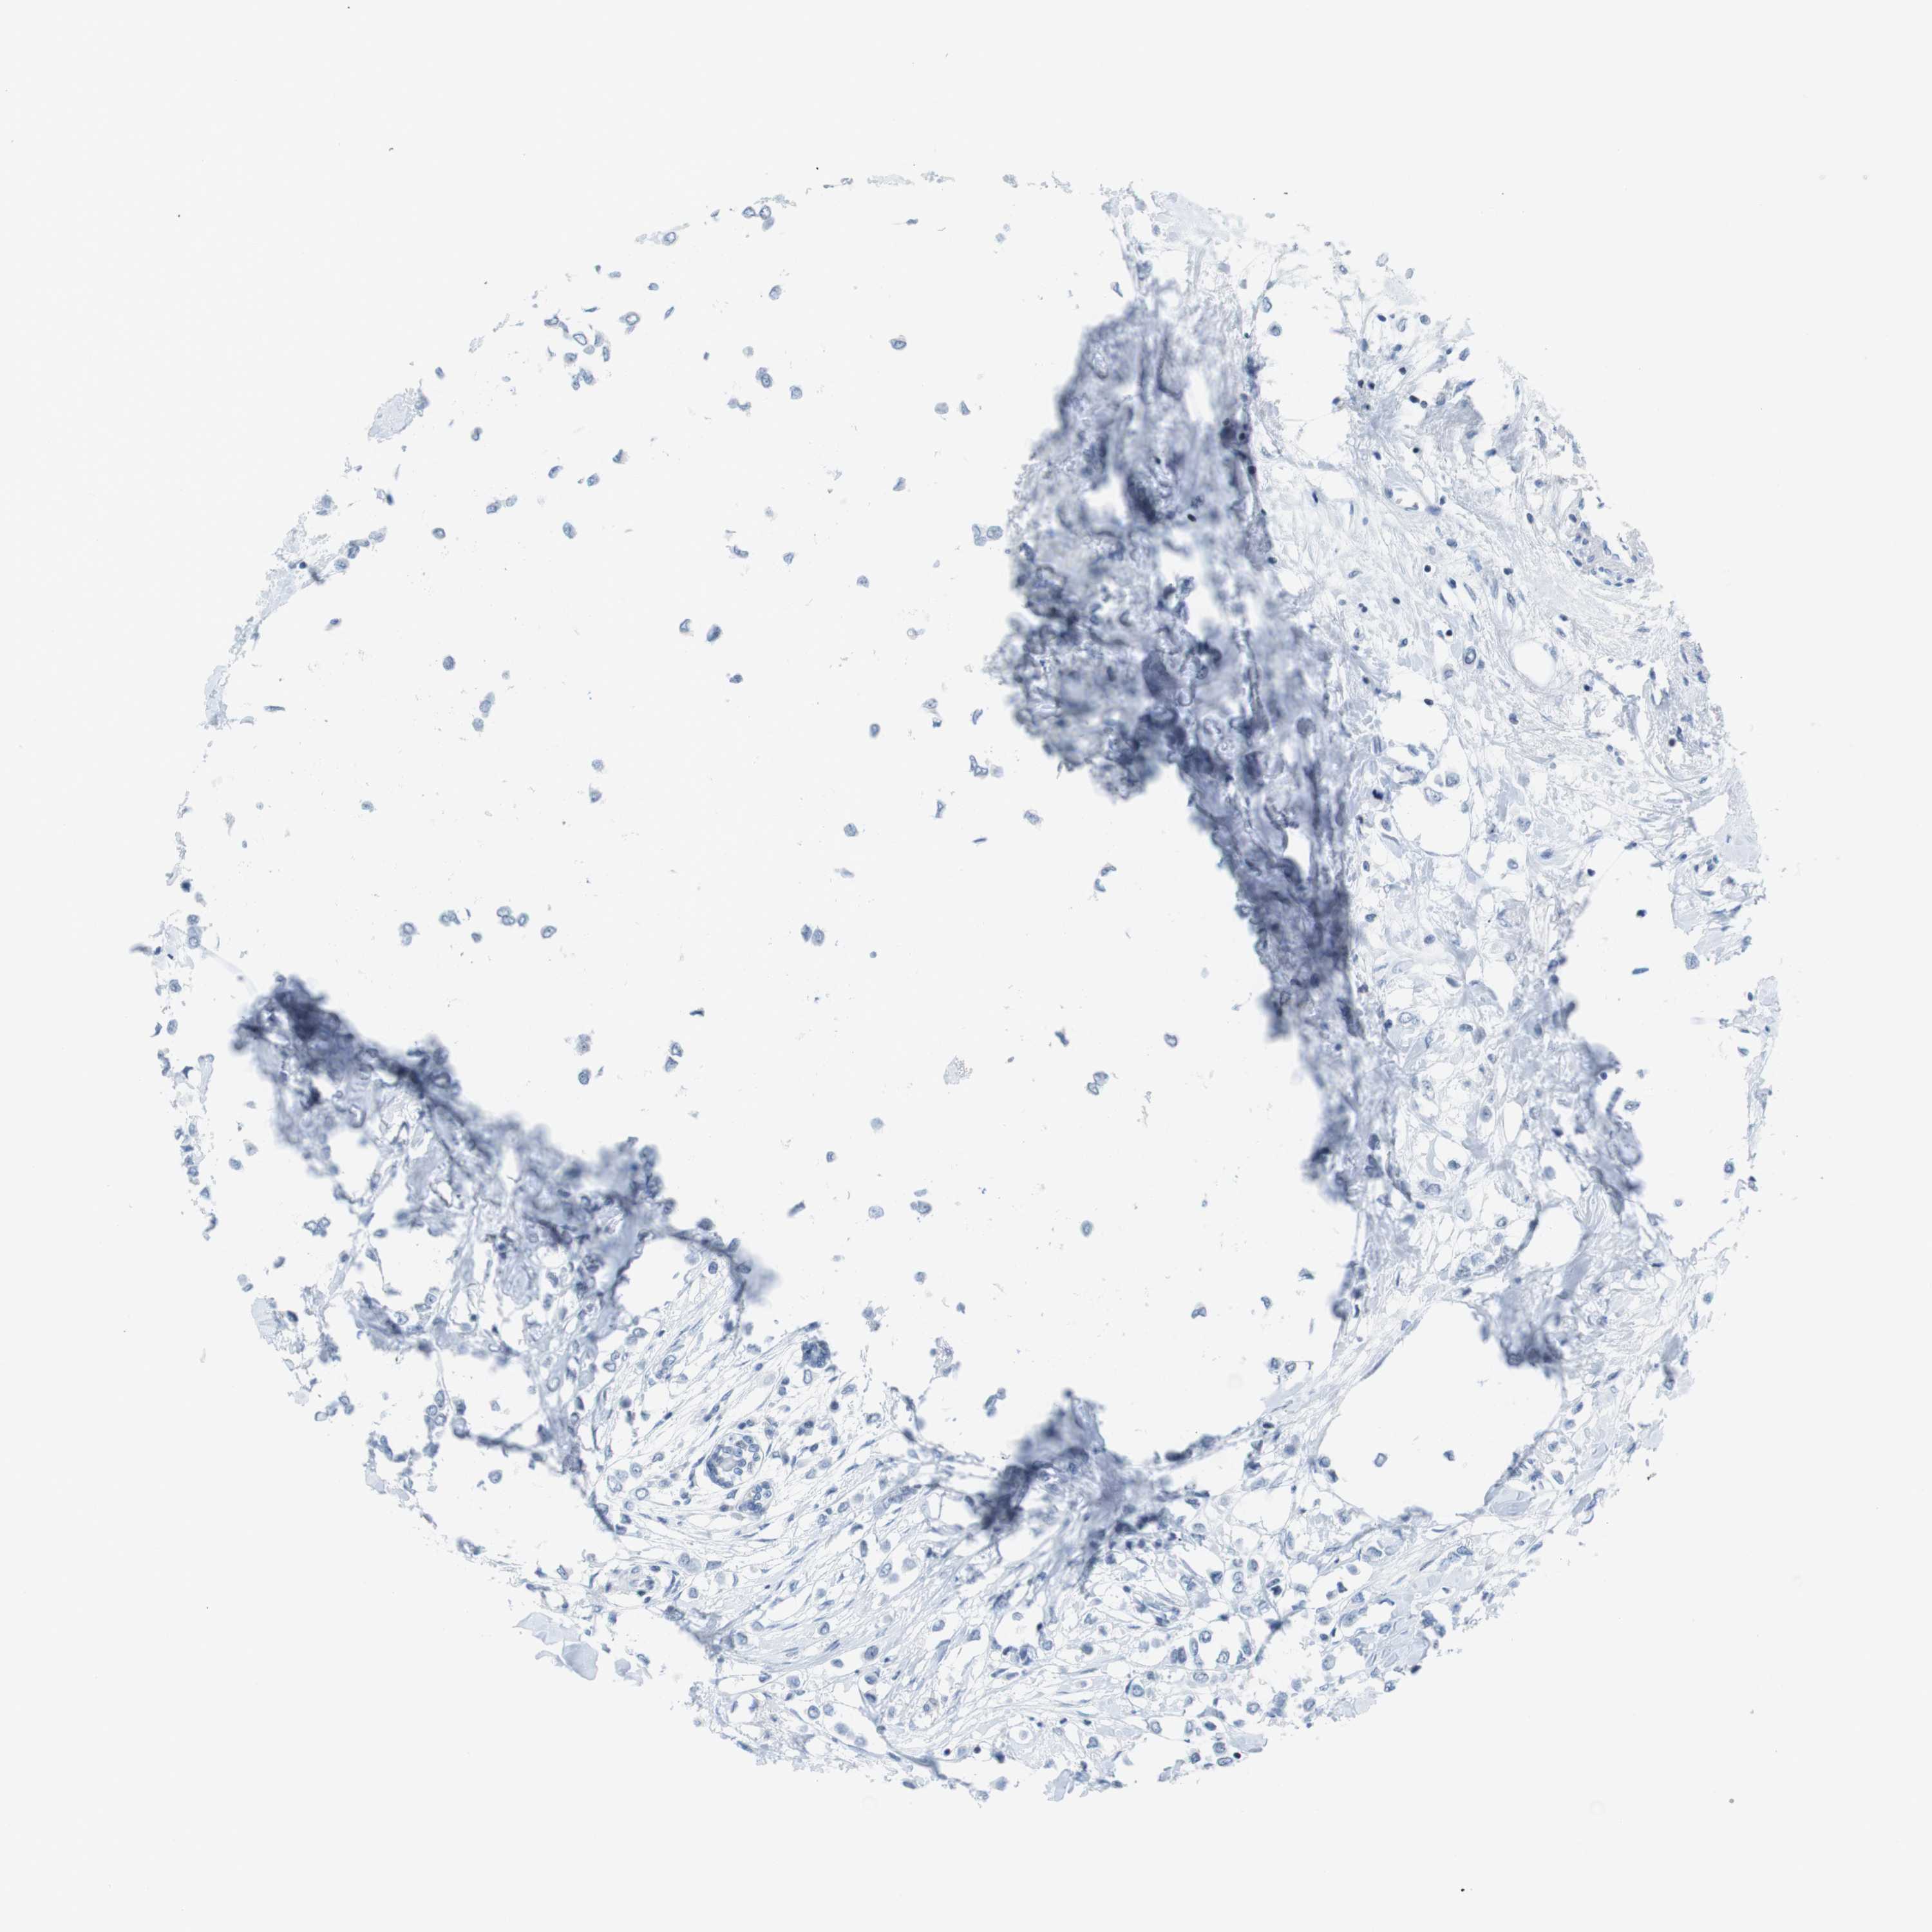

CANCER BREAST CANCER Show tissue menu

BRCA TCGA BRCA VALIDATION PROTEIN EXPRESSION

Breast cancer

Human cancer